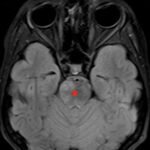

There is a growing body of literature and scientific discovery on pediatric autoimmune encephalitides. This is a heterogenous group of neuroinflammatory conditions leading to often perplexing acute and progressive neurologic and/or neuropsychiatric symptoms. This report demonstrates the evaluation and management of an adolescent with myelin-oligodendrocyte glycoprotein (MOG) antibody-associated fulminant acute disseminated encephalomyelitis (ADEM) in the context of current literature. The featured magnetic resonance imaging uniquely highlights progressive central nervous system lesions detected over the course of the first week of disease.